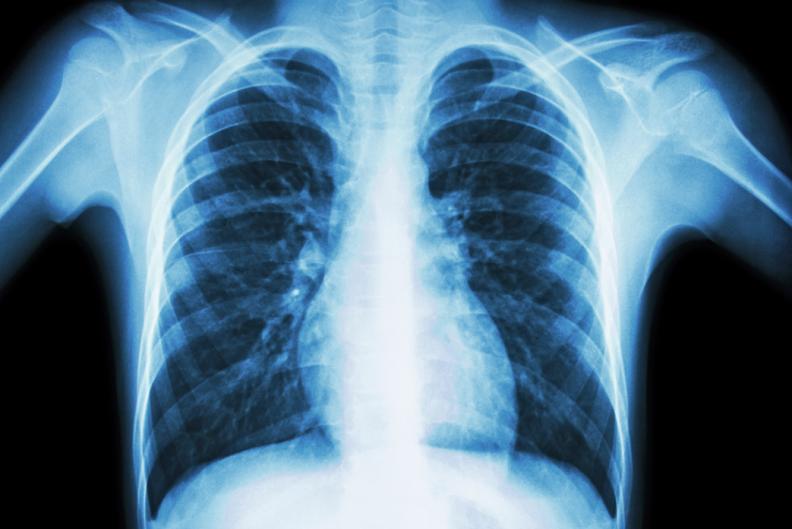

In diesem Kurs wirst du darauf vorbereitet, medizinische Röntgenanlagen unter der verantwortlichen Leitung eines Arztes oder einer Ärztin zu bedienen, wobei ausschliesslich Aufnahmen der Extremitäten und des Thorax gestattet sind.

Röntgenkurs für Aufnahmen von Extremitäten und Thorax (auch Ausgleichsmassnahme Anerkennung ausländischer Ausbildungen SBFI)

- Einstelltechnik von 50 Aufnahmen (Thorax, obere und untere Extremitäten)

- Bildbeurteilung/Anatomie